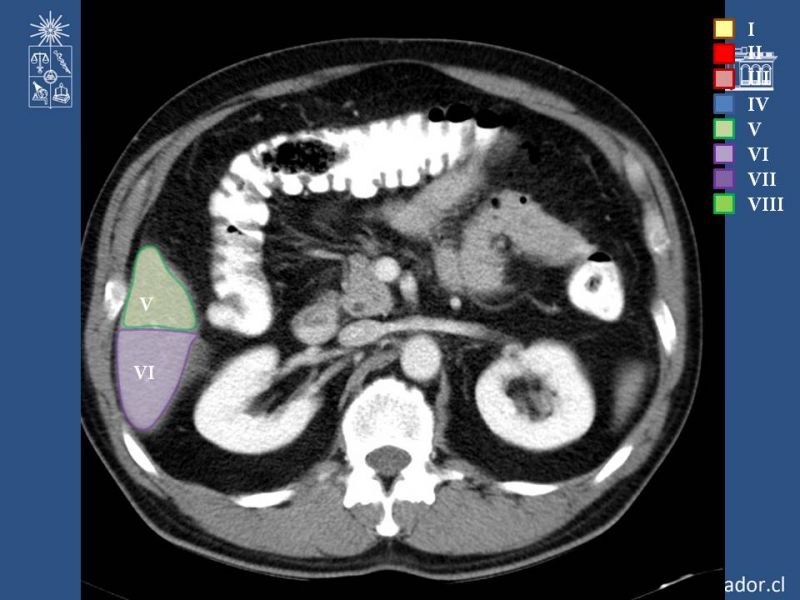

Anatomía Hepática

Hepatobiliopancreático

| Autor: Dr. Enrique Aguila Reyes